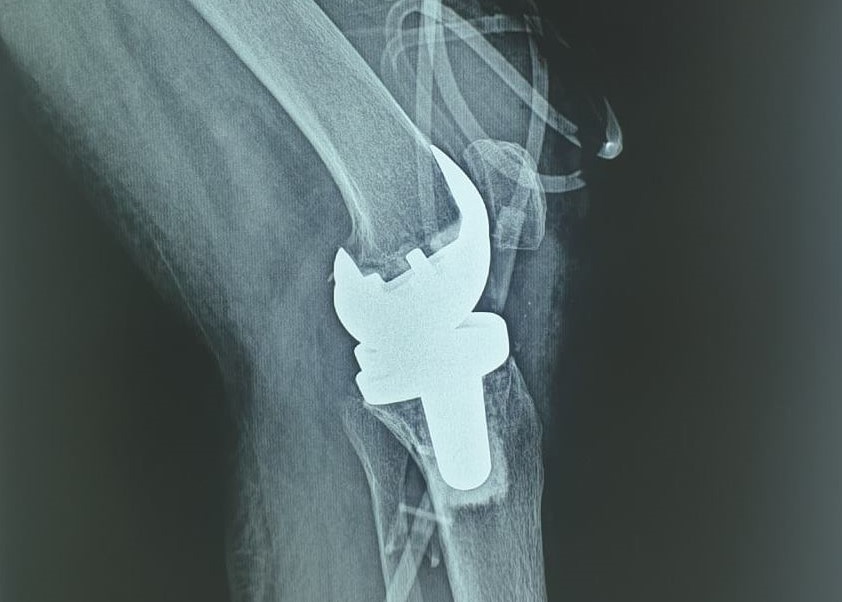

Lần đầu tiên thay thành công khớp gối nhân tạo cho bệnh nhân lao

Sau 17 năm chung sống với bệnh viêm khớp dạng thấp, bệnh nhân đã có thể đi lại bình thường sau khi được thay khớp gối nhân tạo.